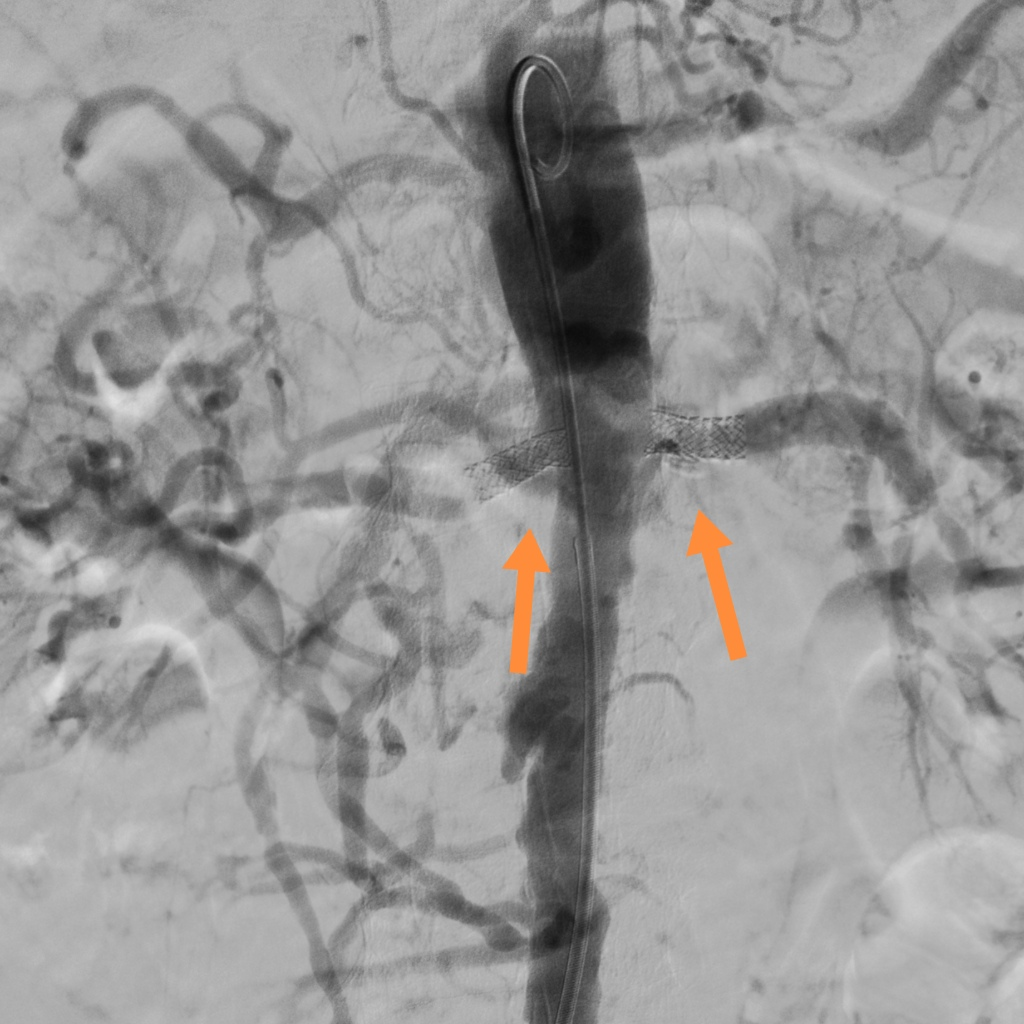

注:支架置入术后肾动脉管腔通畅